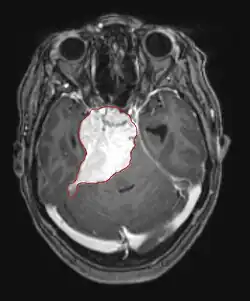

Durch Computertomographie (CT) und Kernspinresonanztomographie (MRT) kann eine Neoplasie im Gehirn effektiv nachgewiesen werden. Zur Identifizierung von Läsionen ist die MRT empfindlicher als die CT, weist aber für Patienten mit Herzschrittmachern, inkompatiblen Prothesen, Metallklammern und anderem Kontraindikationen auf. Die CT bleibt die Methode der Wahl, um Verkalkungen innerhalb der Läsionen oder Knochenerosionen der Schädeldecke oder -basis zu erkennen. Die Verwendung von Kontrastmitteln, die im Fall der CT jodiert und im Fall der MRT paramagnetisch (Gadolinium) sind, ermöglicht die Erfassung von Informationen über die Vaskularisation und Integrität der Blut-Hirn-Schranke, eine bessere Definition der Tumorgeschwulst im Vergleich zum umgebenden Ödem und die Erstellung von Hypothesen über den Grad der Malignität. Die radiologische Untersuchung ermöglicht auch eine Bewertung der mechanischen Auswirkungen und die daraus resultierenden Veränderungen der Gehirnstrukturen, die sich durch den Tumor ergeben, wie zum Beispiel Hydrocephalus und Hernien, deren Auswirkungen tödlich sein können. Schließlich kann mit dieser Diagnostik in Vorbereitung einer Operation der Ort der Läsion oder die Infiltration des Tumors in lebenswichtige Bereiche des Gehirns bestimmt werden. Zu diesem Zweck ist die MRT effizienter als die CT, da sie dreidimensionale Bilder liefern kann.[4]

Diagnostische radiologische Bildgebungsinstrumente heben die Veränderung des neoplastischen Gewebes im Vergleich zum normalen Gehirnparenchym hervor (durch Änderungen der elektronisch dargestellten Dichte des Gewebes bei der CT und der Signalintensität bei der MRT). Wie die meisten pathologischen Gewebe sind auch Tumoren durch eine erhöhte Ansammlung intrazellulären Wassers erkennbar. Im Computertomogramm erscheinen sie hypodens, das heißt von geringerer Dichte als das Gehirnparenchym, im Kernspinresonanztomogramm bei Spin-Gitter-Relaxation hypointens und bei Spin-Spin-Relaxation sowie Protonengewichtung (PD) hyperintens.[5][6]

Auf einer radiologischen Aufnahme sollte der gesunde Gehirnbereich keine besondere Lumineszenz aufweisen. Daher ist es selbstverständlich, dass auf größere Kontrastsignalbereiche geachtet wird.

Im Tumorgewebe ist im Allgemeinen der größere Anteil der Kontrastverstärkung auf die besondere Blut-Tumor-Schranke zurückzuführen, die den Durchgang von Iod (CT) und Gadolinium (MRT) in den intratumoralen extravaskulären Interstitialraum ermöglicht. Dadurch steigt das Signal (Dichte oder Intensität) des Tumors. Es sollte jedoch darauf geachtet werden, dass die Kontrastverstärkung die Neoplasie von Periwundödemen nicht mit Sicherheit abgrenzt. Tatsächlich zeigt der anatomisch-pathologische Befund bei malignen infiltrierenden Gliomen Tumorgewebe, wie zum Beispiel beim Glioblastom und anaplastischem Astrozytom, auch jenseits des vasogenen Ödems, das durch die Zerstörung der Blut-Hirn-Schranke durch den Tumor verursacht wird. Letzterer klinischer Zustand ist durch diagnostische Bildgebung schlecht nachweisbar.[5][6]

Die Computertomographie des Gehirns zeigt typischerweise eine Gewebsmasse, die entweder durch Kontrast verstärkt werden kann. Bei der CT erscheinen niedriggradige Gliome normalerweise isodens zum normalen Parenchym und zeigen daher möglicherweise keine Kontrastverstärkung. In ähnlicher Weise sind Läsionen in der Fossa cranii posterior, der hinteren Schädelgrube, im CT schwer zu identifizieren. Folglich sind die Ergebnisse einer solchen Tomographie allein nicht immer für diagnostische Zwecke ausreichend.[4] In zweifelhaften Fällen ist die Verwendung der empfindlicheren Kernspintomographie unerlässlich.

Auf -Kernspintomogrammen erscheint ein intrakranieller Tumor als massive Läsion, die nach Verwendung des Kontrastmittels lumineszierender werden kann. Eine Signalanomalie gibt es jedoch immer in -Kernspintomogrammen, die auf das Vorhandensein einer Neoplasie oder eines vasogenen Ödems hinweist. Normalerweise ist eine stärkere Lumineszenz (Kontrastverstärkung) ein Hinweis auf einen Tumor höheren Malignitätsgrades. Ein Kontrastring ist charakteristisch für ein Glioblastom, wobei der Lumineszenzanteil dem lebenswichtigen Teil des bösartigen Tumors und der dunklere -hypointense Bereich der Gewebenekrose entspricht.[4]